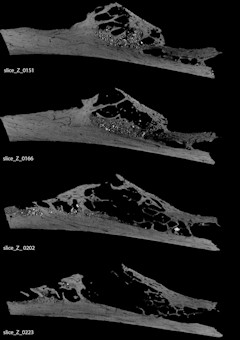

Un estudio publicado este miércoles en la revista 'Plos One' por David Frayer, de la Universidad de Kansas (Estados Unidos) y colegas de otras instituciones, informa del primer caso de un

tumor óseo en las costillas de un

neandertal. Este descubrimiento de una

displasia fibrosa es anterior a la evidencia previa de este tumor de más de 100.000 años, ya que antes de esta investigación, los cánceres más tempranos conocidos de hueso ocurrieron en muestras de aproximadamente entre 1.000 y 4.000 años.

La

nervadura cancerosa, hallada en Krapina (Croacia) es una muestra incompleta, por lo que los investigadores no pudieron determinar los efectos del tumor en la salud en general de este individuo.